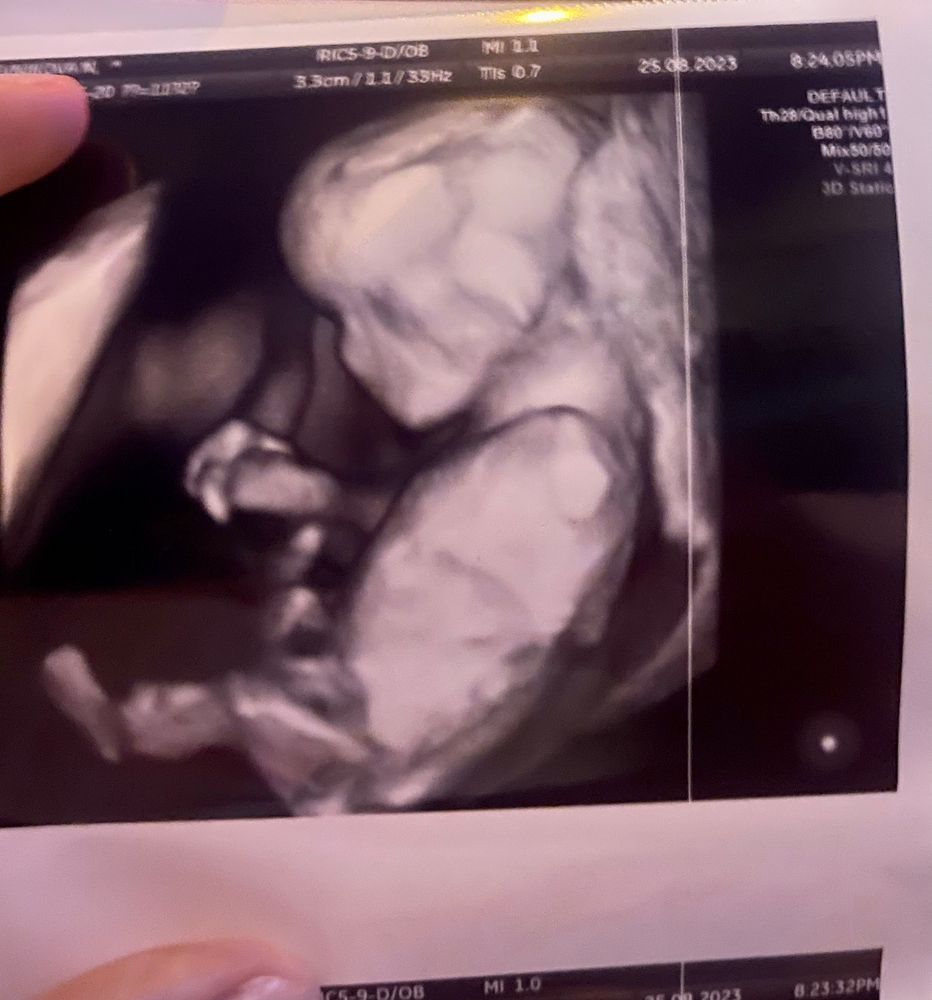

Вчера ходила на узи шейку мониторить, попросила и дочу посмотреть 🥰 записала видео мужу.. лежит принцесса 👸🏼 ногу на ногу руками машет, на мостик встает явно узи ей не нр